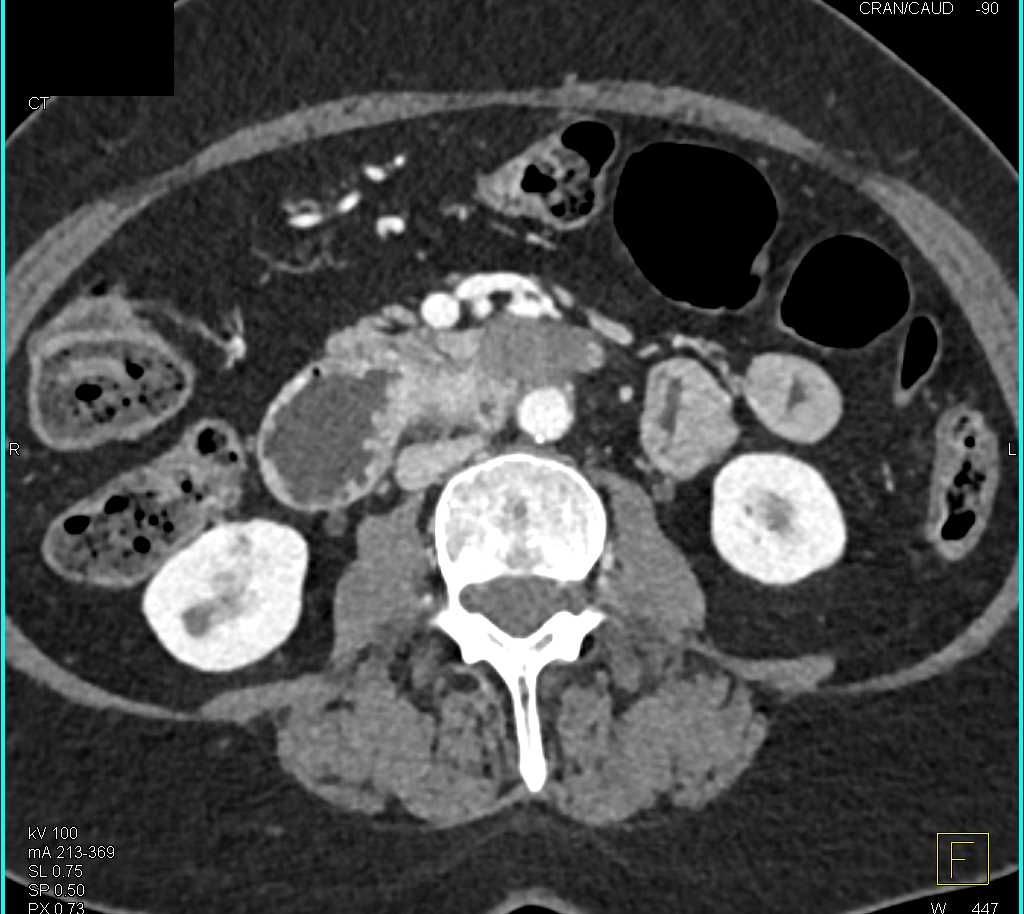

Duodenal Carcinoma with Obstruction